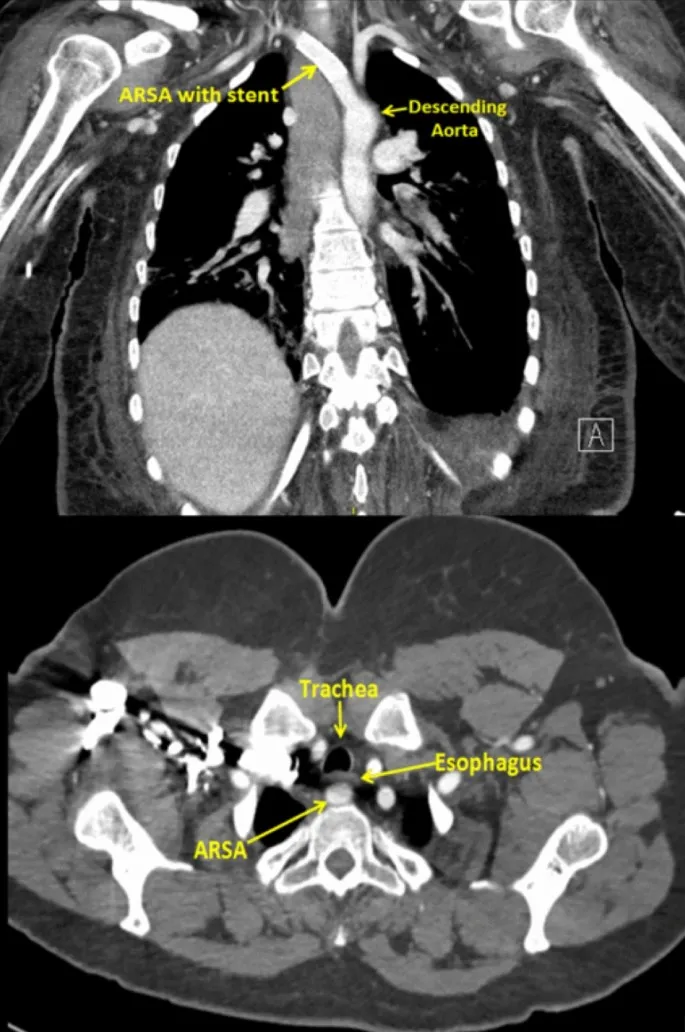

| CVS | Aberrant Rt. Subclavian (Arteria Lusoria) | Last arch branch, retro-esophageal (CT, Barium); Dysphagia. |

⭐ For suspected vascular rings or slings causing tracheoesophageal compression, CT Angiography or MR Angiography are the imaging modalities of choice for definitive diagnosis and surgical planning.

⭐ An aberrant right subclavian artery (arteria lusoria) is a common aortic arch anomaly (~1% population) that can cause dysphagia (dysphagia lusoria) or be an incidental finding. Its presence is critical for thoracic surgery planning.